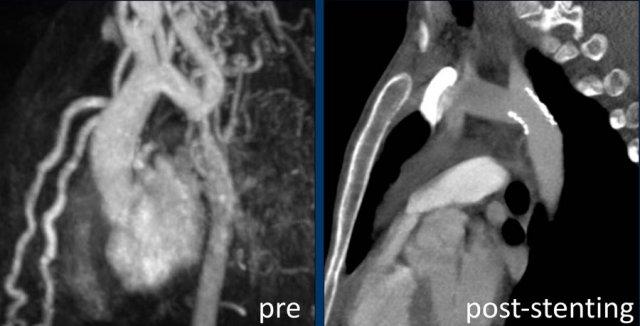

Liệu pháp đặt stent nội mạch được xem là lựa chọn điều trị hàng đầu cho hầu hết người lớn và thanh thiếu niên mắc hẹp eo động mạch chủ (tài liệu tham khảo).

Hình ảnh: stent nội mạch ở vị trí tốt.

Hình ảnh MRA của cùng bệnh nhân trước khi đặt stent.

Hình ảnh CTA sau khi đặt stent.